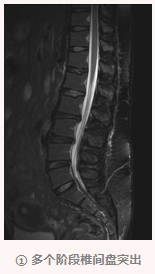

随后唐姐慕名来到我院骨伤科汪青春教授处就诊,确诊为腰椎间盘突出症、腰臀肌筋膜炎。

我院骨伤科学术带头人汪青春教授表示,腰椎间盘突出症和腰臀肌筋膜炎往往伴随出现,治疗需要兼顾,该病发病率较高,特别是长时间坐位工作的人群,手术治疗并非首选,大部分患者可以通过规范的保守治疗取得良好效果。